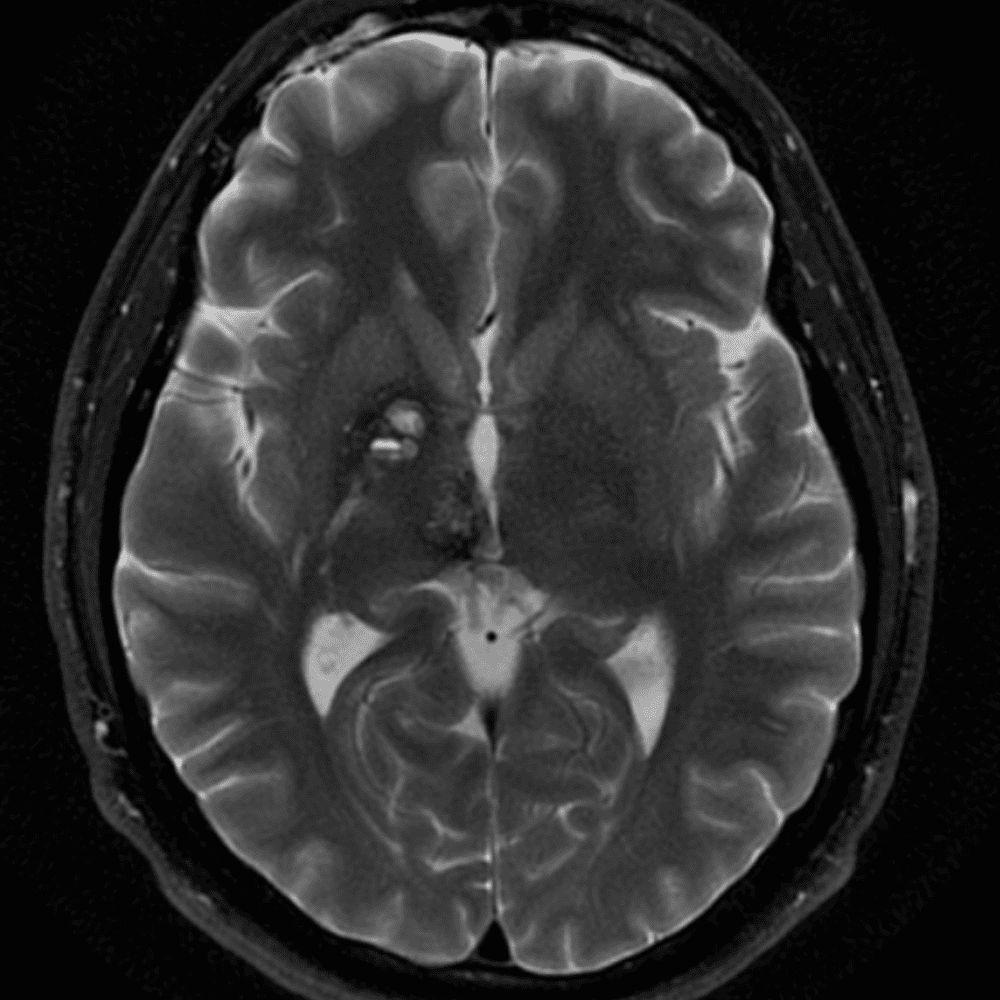

๋‹น์ง ์‹œ ํ”ํžˆ ๋ณผ ์ˆ˜ ์žˆ๋Š” ์‚ฌ๋ก€์˜ ์ „ํ˜•์ ์ธ ์˜ˆ๋ฅผ ํฌํ•จํ•ฉ๋‹ˆ๋‹ค.

39 ์‚ฌ๋ก€

์—ฐ์Šต

๋ฏธ๋ฌ˜ํ•˜๊ฑฐ๋‚˜ ์–ด๋ ค์šด ์‚ฌ๋ก€์™€ ์ผ๋ถ€ ์ •์ƒ ์‚ฌ๋ก€๋ฅผ ํฌํ•จํ•˜์—ฌ ๋‹น์ง์„ ์‹œ๋ฎฌ๋ ˆ์ด์…˜ํ•ฉ๋‹ˆ๋‹ค.

50 ์‚ฌ๋ก€